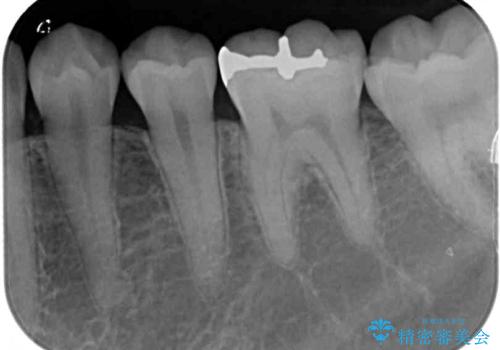

- 奥歯の銀歯と虫歯を気にして来院された患者様です。

下顎は口を開けたときに目立つためセラミックインレーに、上顎奥歯は機能面を優先してゴールドインレーにて修復治療を行うこととしました。

機能面を優先すると、PGAインレー(ゴールドインレー)による修復治療やPGAクラウンによる補綴治療が望ましいのですが、笑ったときに見えている銀歯がどうしても気なってしまうとのことで、目立ってしまう奥歯はセラミックインレーやセラミッククラウンを装着することとしました。